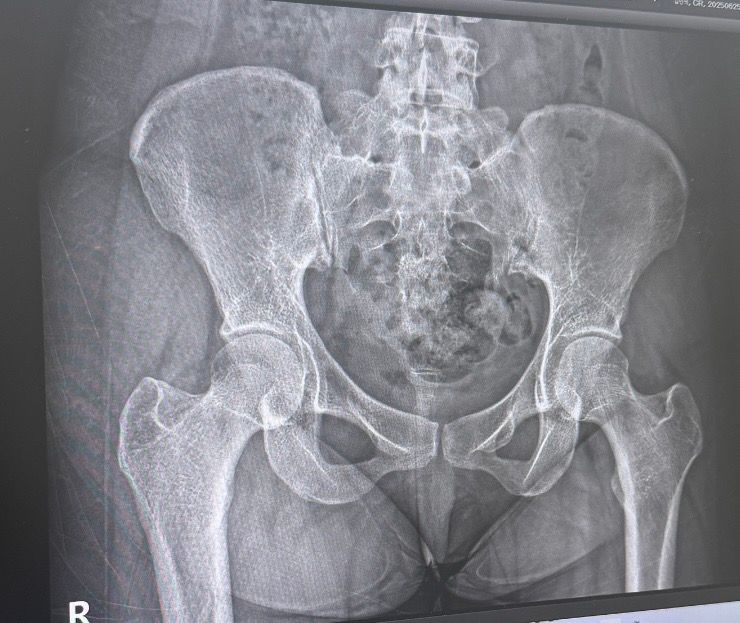

정형외과에서 엑스레이 찍은 사진인데요 골반과 고관절이 큰 편 인가요???? 아님 작은편인가요???………………………….

사진상 골반뼈와 고관절은 특별히 비정상적으로 크거나 작아 보이지 않습니다.

좌우 대칭 및 관절 간격도 비교적 정상 범위로 보입니다.

하지만, 이는 단순 시각적 평가일 뿐, 실제 크기(수치)는 전문의가 직접 측정한 값(대퇴골두 간 거리, 골반 외측 간 거리 등) 이 필요합니다.